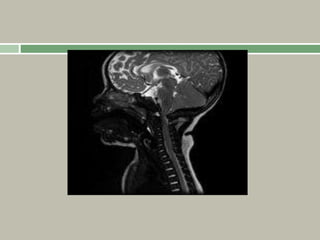

Foramen magnum hypoplasia can cause

craniocervical stenosis, which may cause

hypotonia, sleep apnoea or even sudden death.

Thoracolumbar kyphosis is commonly seen in

infants, but usually resolves with growth and

maturity as muscle tone improves.

Achondroplasia

While stenosis of the spinal canal occurs in all

patients

with achondroplasia (secondary to thickening of the

pedicles, hypertrophy of the facets and enlarged

laminae), not all will develop symptoms due to this.